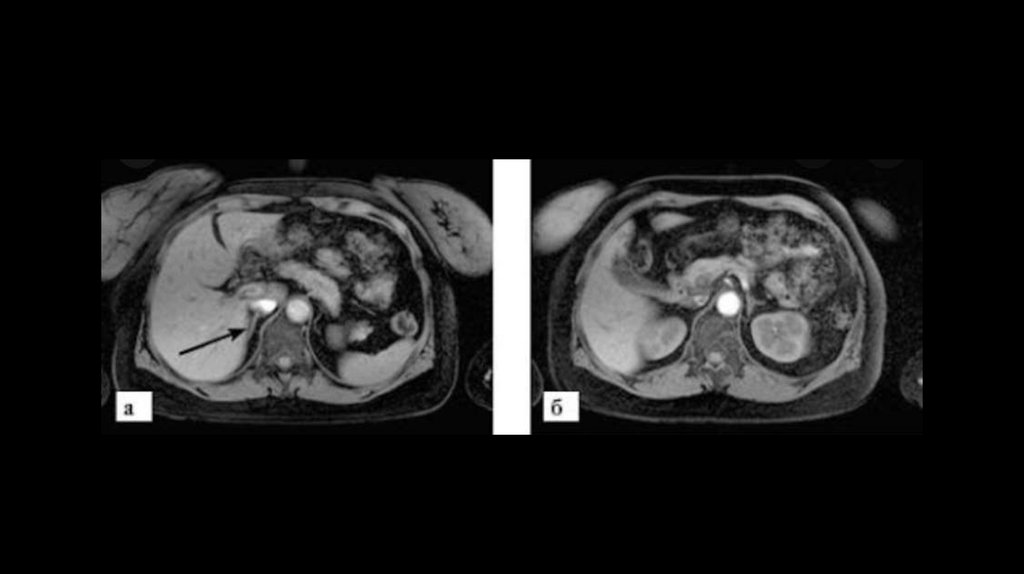

20. МРТ/КТ

• ◊ При МРТ в сочетании с контрастированием гипофиза

(гадолиний) аденома выявляется в 80% случаев.

• ◊ Однако следует иметь в виду, что аденома гипофиза выявляется

у 10% лиц без нарушения функции гипофиза, поэтому

биохимические исследования гормонов имеют решающее

значение.

• ◊ В случае подозрения на АКТГ-независимый синдром Иценко –

Кушинга при МРТ/КТ в надпочечниках можно выявить

характерные морфологические изменения.